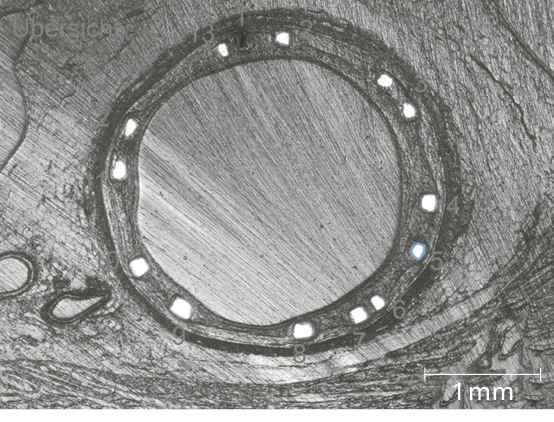

Predictable, homogeneous resorption process6

Equal resorption between struts6

Uniform shape due to homogeneous strut resorption6

More than 3 months vessel support6,7

>99% of struts no longer visible at 12 months8

Markers One oval Tantalum marker at each end